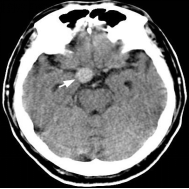

未破裂的脑动脉瘤的CT典型表现 破裂的脑动脉瘤 CT表现(SAH)